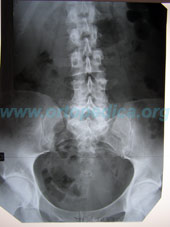

Рентгенограмма поясничного отдела позвоночника в прямой проекции

Рентгенограмма поясничного отдела позвоночника в боковой проекции